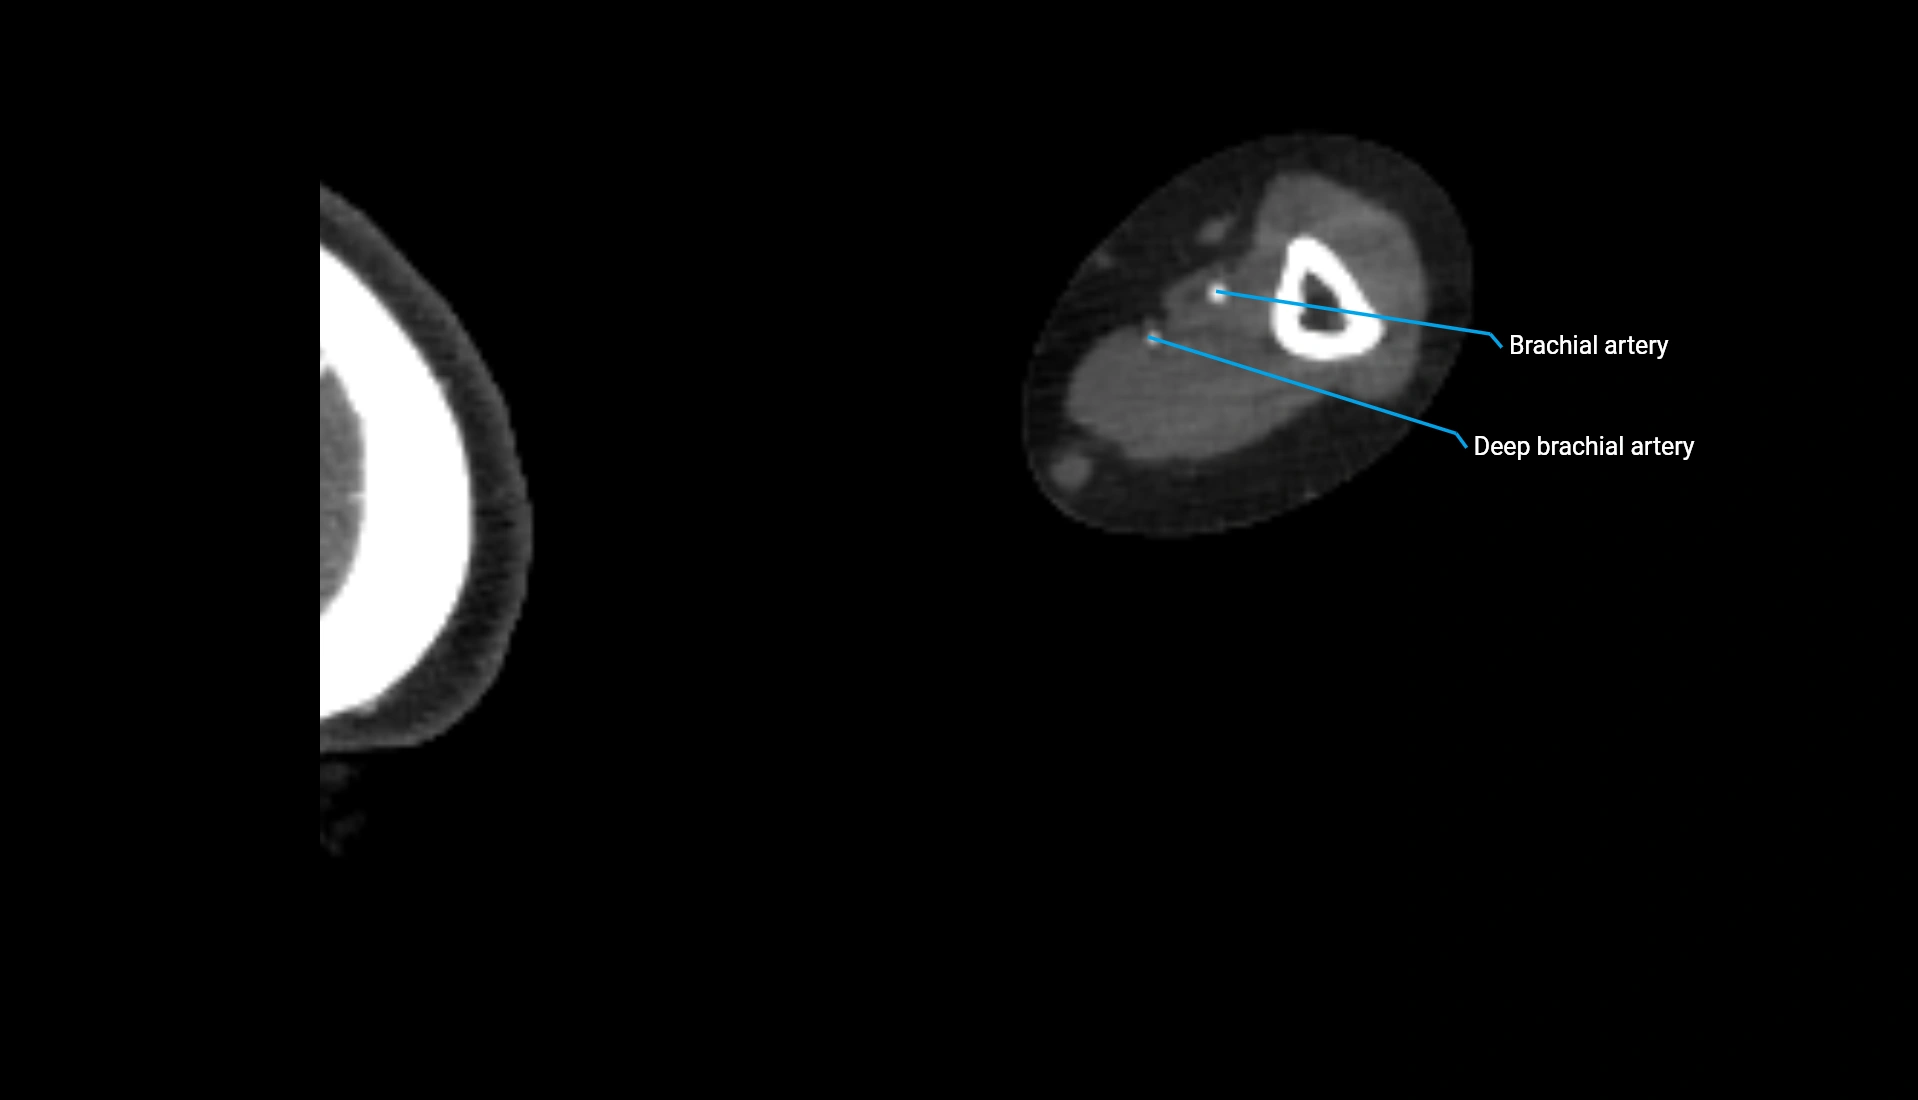

CT Appearance

Non-Contrast CT:

• Cortex: High-density, sharply defined

• Subchondral bone: Dense cancellous matrix

• Articular surface: Smooth concave contour articulating with the capitellum

• Excellent for evaluating bone integrity, alignment, and subtle fractures